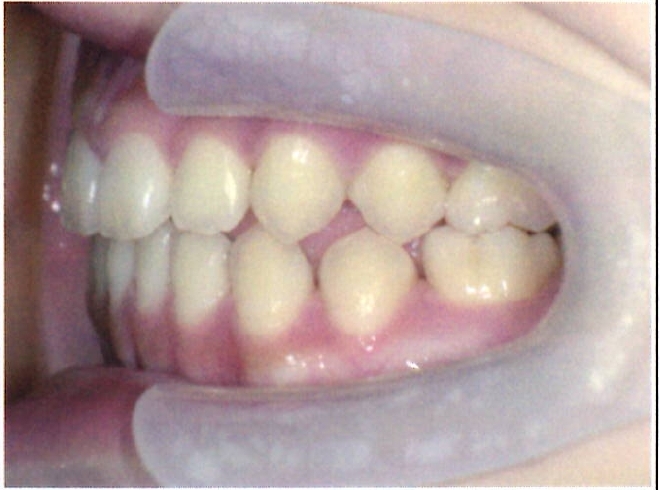

| 主訴・治療前の状態 | 著しい叢生(歯並びのガタガタ)があり、また6歳臼歯(第一大臼歯)が破折していた状態でした。 |

| 治療内容 | 通常の抜歯矯正では第一小臼歯(4番)を抜歯することが多く、その方が治療期間を短縮できますが、小川さんの場合は破折していた6歳臼歯を抜歯し、そのスペースを活用して歯列を整えました。これにより、健康な歯の本数を維持しながら矯正治療を行うことができました。 |

| 治療結果 | 治療前と比較して歯並びが大きく改善し、見た目も大幅に良くなりました。患者様にも大変喜んでいただけた症例です。 |